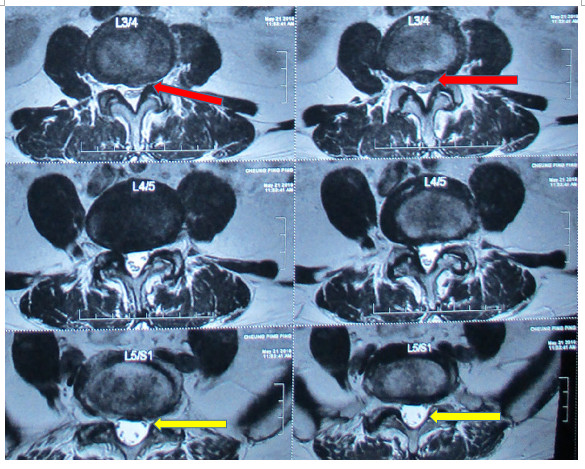

之後筆者在診所內幫她拍磁力共振掃描,發現她的症狀不是因為腰椎第五節有椎間盤突出及狹窄(雖然從X光中見到腰椎第五節與骶骨第一節空間真的變小,但也未必能判斷就是腰椎第五節椎間盤突出),反而見到的是腰椎第三、四節間椎間盤突出及椎管狹窄,並壓着左邊神經根而引起她的左腳麻痺疼痛,而且發現她的腰椎第五節椎間盤沒有突出,椎管亦沒有狹窄的情況

透過磁力共振掃描,可見到案例二患者腰椎第三、四節椎間盤突出及椎管狹窄壓着左邊神經根,而不是X光看到的腰椎第五節的問題